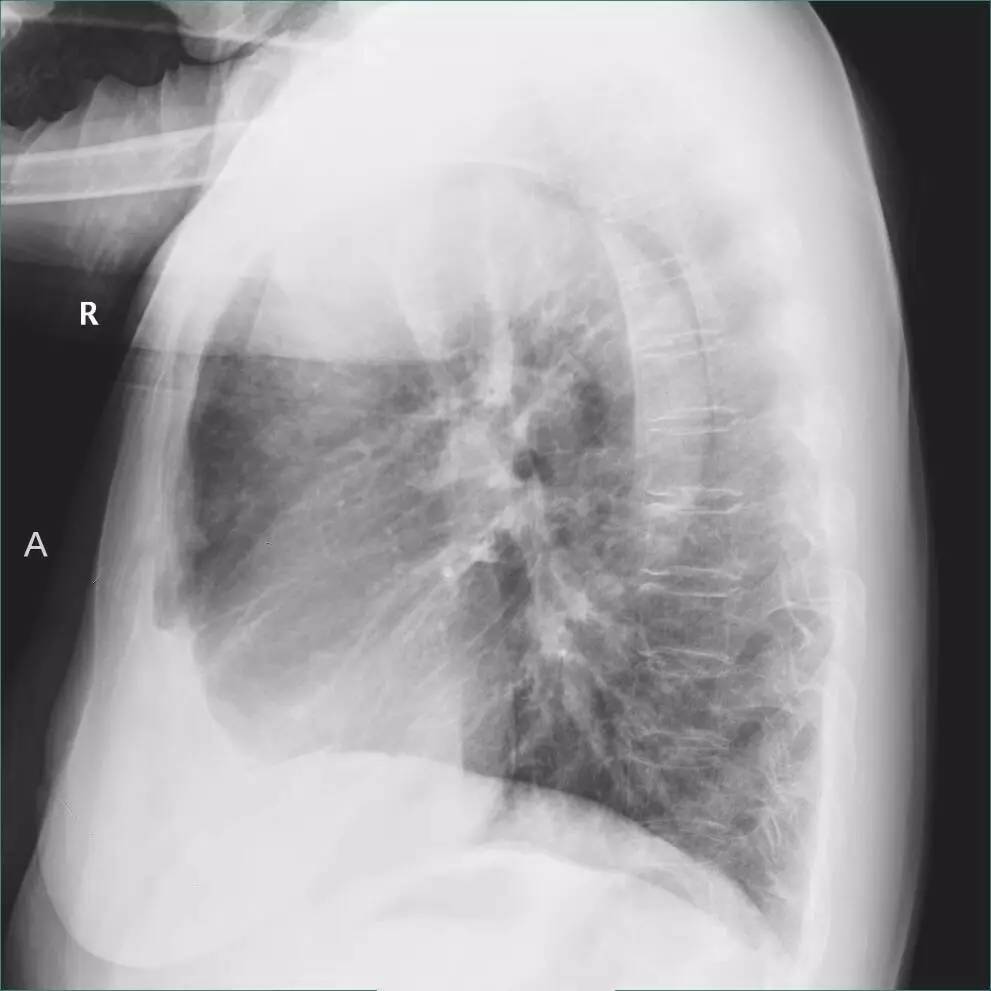

一张二维的胸片中,肋膈角处的异常是胸膜增厚?还是少量胸腔积液,还是模模糊糊分不清?

>>>>病例2:男,88y,右侧胸痛月余。

左下肺最有可能的诊断是?

A.包裹性积液

B.胸膜增厚

C.胸腔积液

D.心包脂肪垫